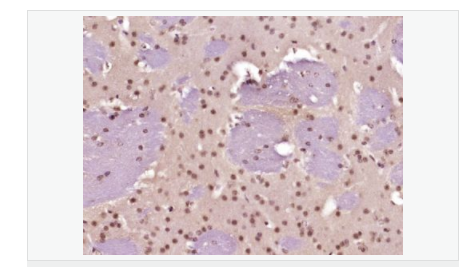

| 產(chǎn)品應(yīng)用 | WB=1:500-2000 ELISA=1:5000-10000 IHC-P=1:100-500 IHC-F=1:100-500 Flow-Cyt=1ug/Test ICC=1:100-500 IF=1:100-500 (石蠟切片需做抗原修復(fù)) not yet tested in other applications. optimal dilutions/concentrations should be determined by the end user. |

| 細(xì)胞定位 | 細(xì)胞核 |

| 產(chǎn)品介紹 | This gene encodes a member of the Notch family. Members of this Type 1 transmembrane protein family share structural characteristics including an extracellular domain consisting of multiple epidermal growth factor-like (EGF) repeats, and an intracellular domain consisting of multiple, different domain types. Notch family members play a role in a variety of developmental processes by controlling cell fate decisions. The Notch signaling network is an evolutionarily conserved intercellular signaling pathway which regulates interactions between physically adjacent cells. In Drosophilia, notch interaction with its cell-bound ligands (delta, serrate) establishes an intercellular signaling pathway that plays a key role in development. Homologues of the notch-ligands have also been identified in human, but precise interactions between these ligands and the human notch homologues remain to be determined. This protein is cleaved in the trans-Golgi network, and presented on the cell surface as a heterodimer. This protein functions as a receptor for membrane bound ligands, and may play multiple roles during development. [provided by RefSeq, Jul 2008]. Function: Notch family members play a role in a variety of developmental processes by controlling cell fate decisions. The Notch signaling network is an evolutionarily conserved intercellular signaling pathway which regulates interactions between physically adjacent cells. The protein is cleaved in the trans-Golgi network, and presented on the cell surface as a heterodimer. This protein functions as a receptor for membrane bound ligands. Once the Notch extracellular domain interacts with a ligand, a protease called TACE (Tumor Necrosis Factor Alpha Converting Enzyme) cleaves the Notch protein just outside the membrane. This releases the extracellular portion of Notch, which continues to interact with the ligand. The ligand plus the Notch extracellular domain is then endocytosed by the ligand expressing cell. After this first cleavage, an enzyme called gamma-secretase cleaves the remaining part of the Notch protein just inside the inner leaflet of the cell membrane. This releases the intracellular portion of the Notch protein, which then moves to the nucleus and causes various genes to be expressed. There are many other proteins involved in the intracellular portion of the Notch signalling cascade. Subunit: Heterodimer of a C-terminal fragment N(TM) and an N-terminal fragment N(EC) which are probably linked by disulfide bonds. Interacts with DNER, DTX1, DTX2 and RBPJ/RBPSUH. Also interacts with MAML1, MAML2 and MAML3 which act as transcriptional coactivators for NOTCH1. The activated membrane-bound form interacts with AAK1 which promotes NOTCH1 stabilization. Forms a trimeric complex with FBXW7 and SGK1. Interacts with HIF1AN. HIF1AN negatively regulates the function of notch intracellular domain (NICD), accelerating myogenic differentiation. Subcellular Location: Cell membrane; Single-pass type I membrane protein. Notch 1 intracellular domain: Nucleus. Note=Following proteolytical processing NICD is translocated to the nucleus. Tissue Specificity: In fetal tissues most abundant in spleen, brain stem and lung. Also present in most adult tissues where it is found mainly in lymphoid tissues. Post-translational modifications: Synthesized in the endoplasmic reticulum as an inactive form which is proteolytically cleaved by a furin-like convertase in the trans-Golgi network before it reaches the plasma membrane to yield an active, ligand-accessible form. Cleavage results in a C-terminal fragment N(TM) and a N-terminal fragment N(EC). Following ligand binding, it is cleaved by TNF-alpha converting enzyme (TACE) to yield a membrane-associated intermediate fragment called notch extracellular truncation (NEXT). Following endocytosis, this fragment is then cleaved by presenilin dependent gamma-secretase to release a notch-derived peptide containing the intracellular domain (NICD) from the membrane (By similarity). Phosphorylated (By similarity). O-glycosylated on the EGF-like domains. Contains both O-linked fucose and O-linked glucose. Ubiquitinated; undergoes 'Lys-29'-linked polyubiquitination catalyzed by ITCH. Monoubiquitination at Lys-1759 is required for activation by gamma-secretase cleavage, it promotes interaction with AAK1, which stabilizes it. Deubiquitination by EIF3F is necessary for nuclear import of activated Notch. Hydroxylated at Asn-1955 by HIF1AN. Hydroxylated at Asn-2022 by HIF1AN (By similarity). Hydroxylation reduces affinity for HI1AN and may thus indirectly modulate negative regulation of NICD. DISEASE: Defects in NOTCH1 are a cause of aortic valve disease 1 (AOVD1) [MIM:109730]. A common defect in the aortic valve in which two rather than three leaflets are present. It is often associated with aortic valve calcification and insufficiency. In extreme cases, the blood flow may be so restricted that the left ventricle fails to grow, resulting in hypoplastic left heart syndrome. Similarity: Belongs to the NOTCH family. Contains 5 ANK repeats. Contains 36 EGF-like domains. Contains 3 LNR (Lin/Notch) repeats. SWISS: P46531 Gene ID: 4851 Database links: Entrez Gene: 4851 Human Entrez Gene: 18128 Mouse Omim: 190198 Human SwissProt: P46531 Human SwissProt: Q01705 Mouse Unigene: 495473 Human nigene: 290610 Mouse Important Note: This product as supplied is intended for research use only, not for use in human, therapeutic or diagnostic applications. |